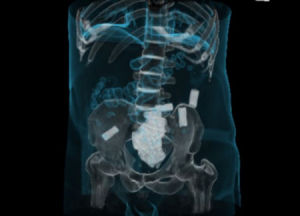

毒騾攜毒方式看過電影《李米的猜想》的人可能還對影片中那個可恨又可憐的“毒騾”印象深刻吧。Mule指的是越境偷運物品的人。偷運的辦法包括藏在運輸工具、行李、衣服內,貼身攜帶和把身體作為容器。最後一種偷運方法一般用於毒品偷運。把身體作為容器的走私者也叫swallower或internalcarrier,這種行為被稱為bodypacking或bodystuffing。